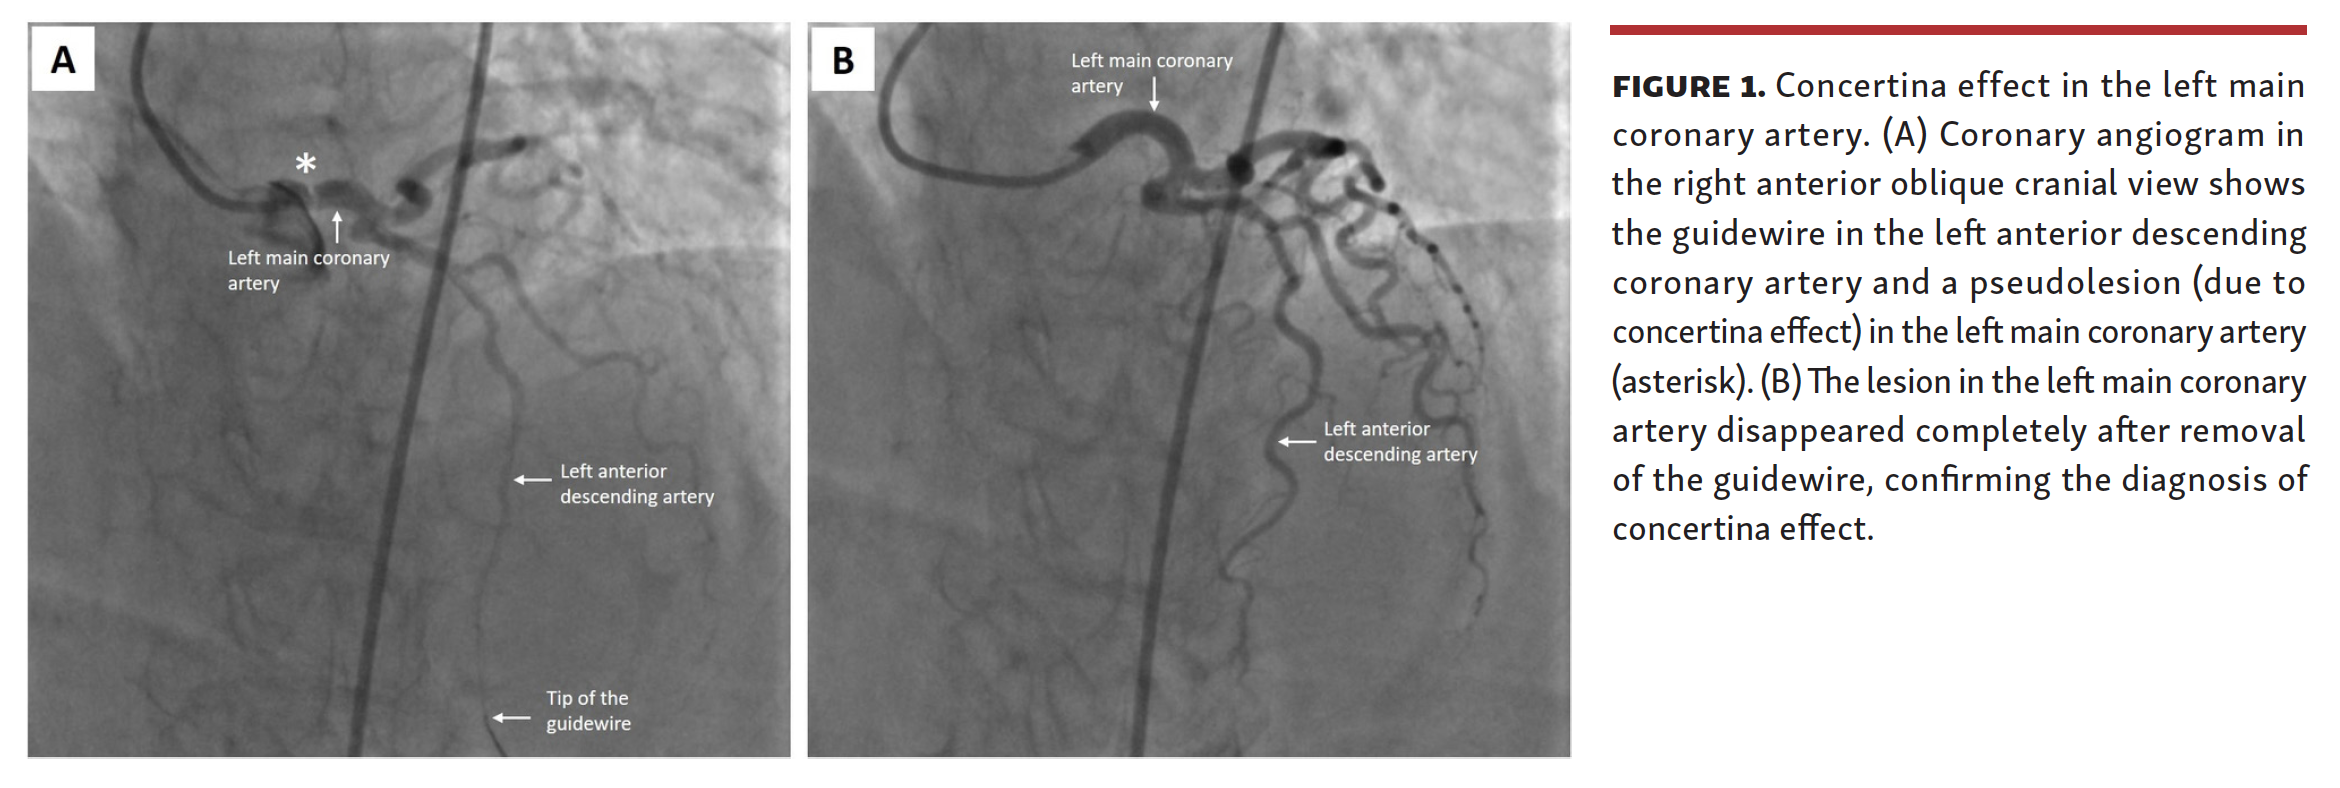

A Phantom Lesion in the Left Main Coronary Artery Concertina Effect Concertina Effect F1 Named after the musical instrument, that compresses and expands, kind of like a line of cars as they go. “it’s a restart, you know, so we don’t know. The concertina effect happens at turns with a trailing car temporarily closing on a car because it's not yet braking. Then the effect is reversed. As a result of the braking, the. Concertina Effect F1.